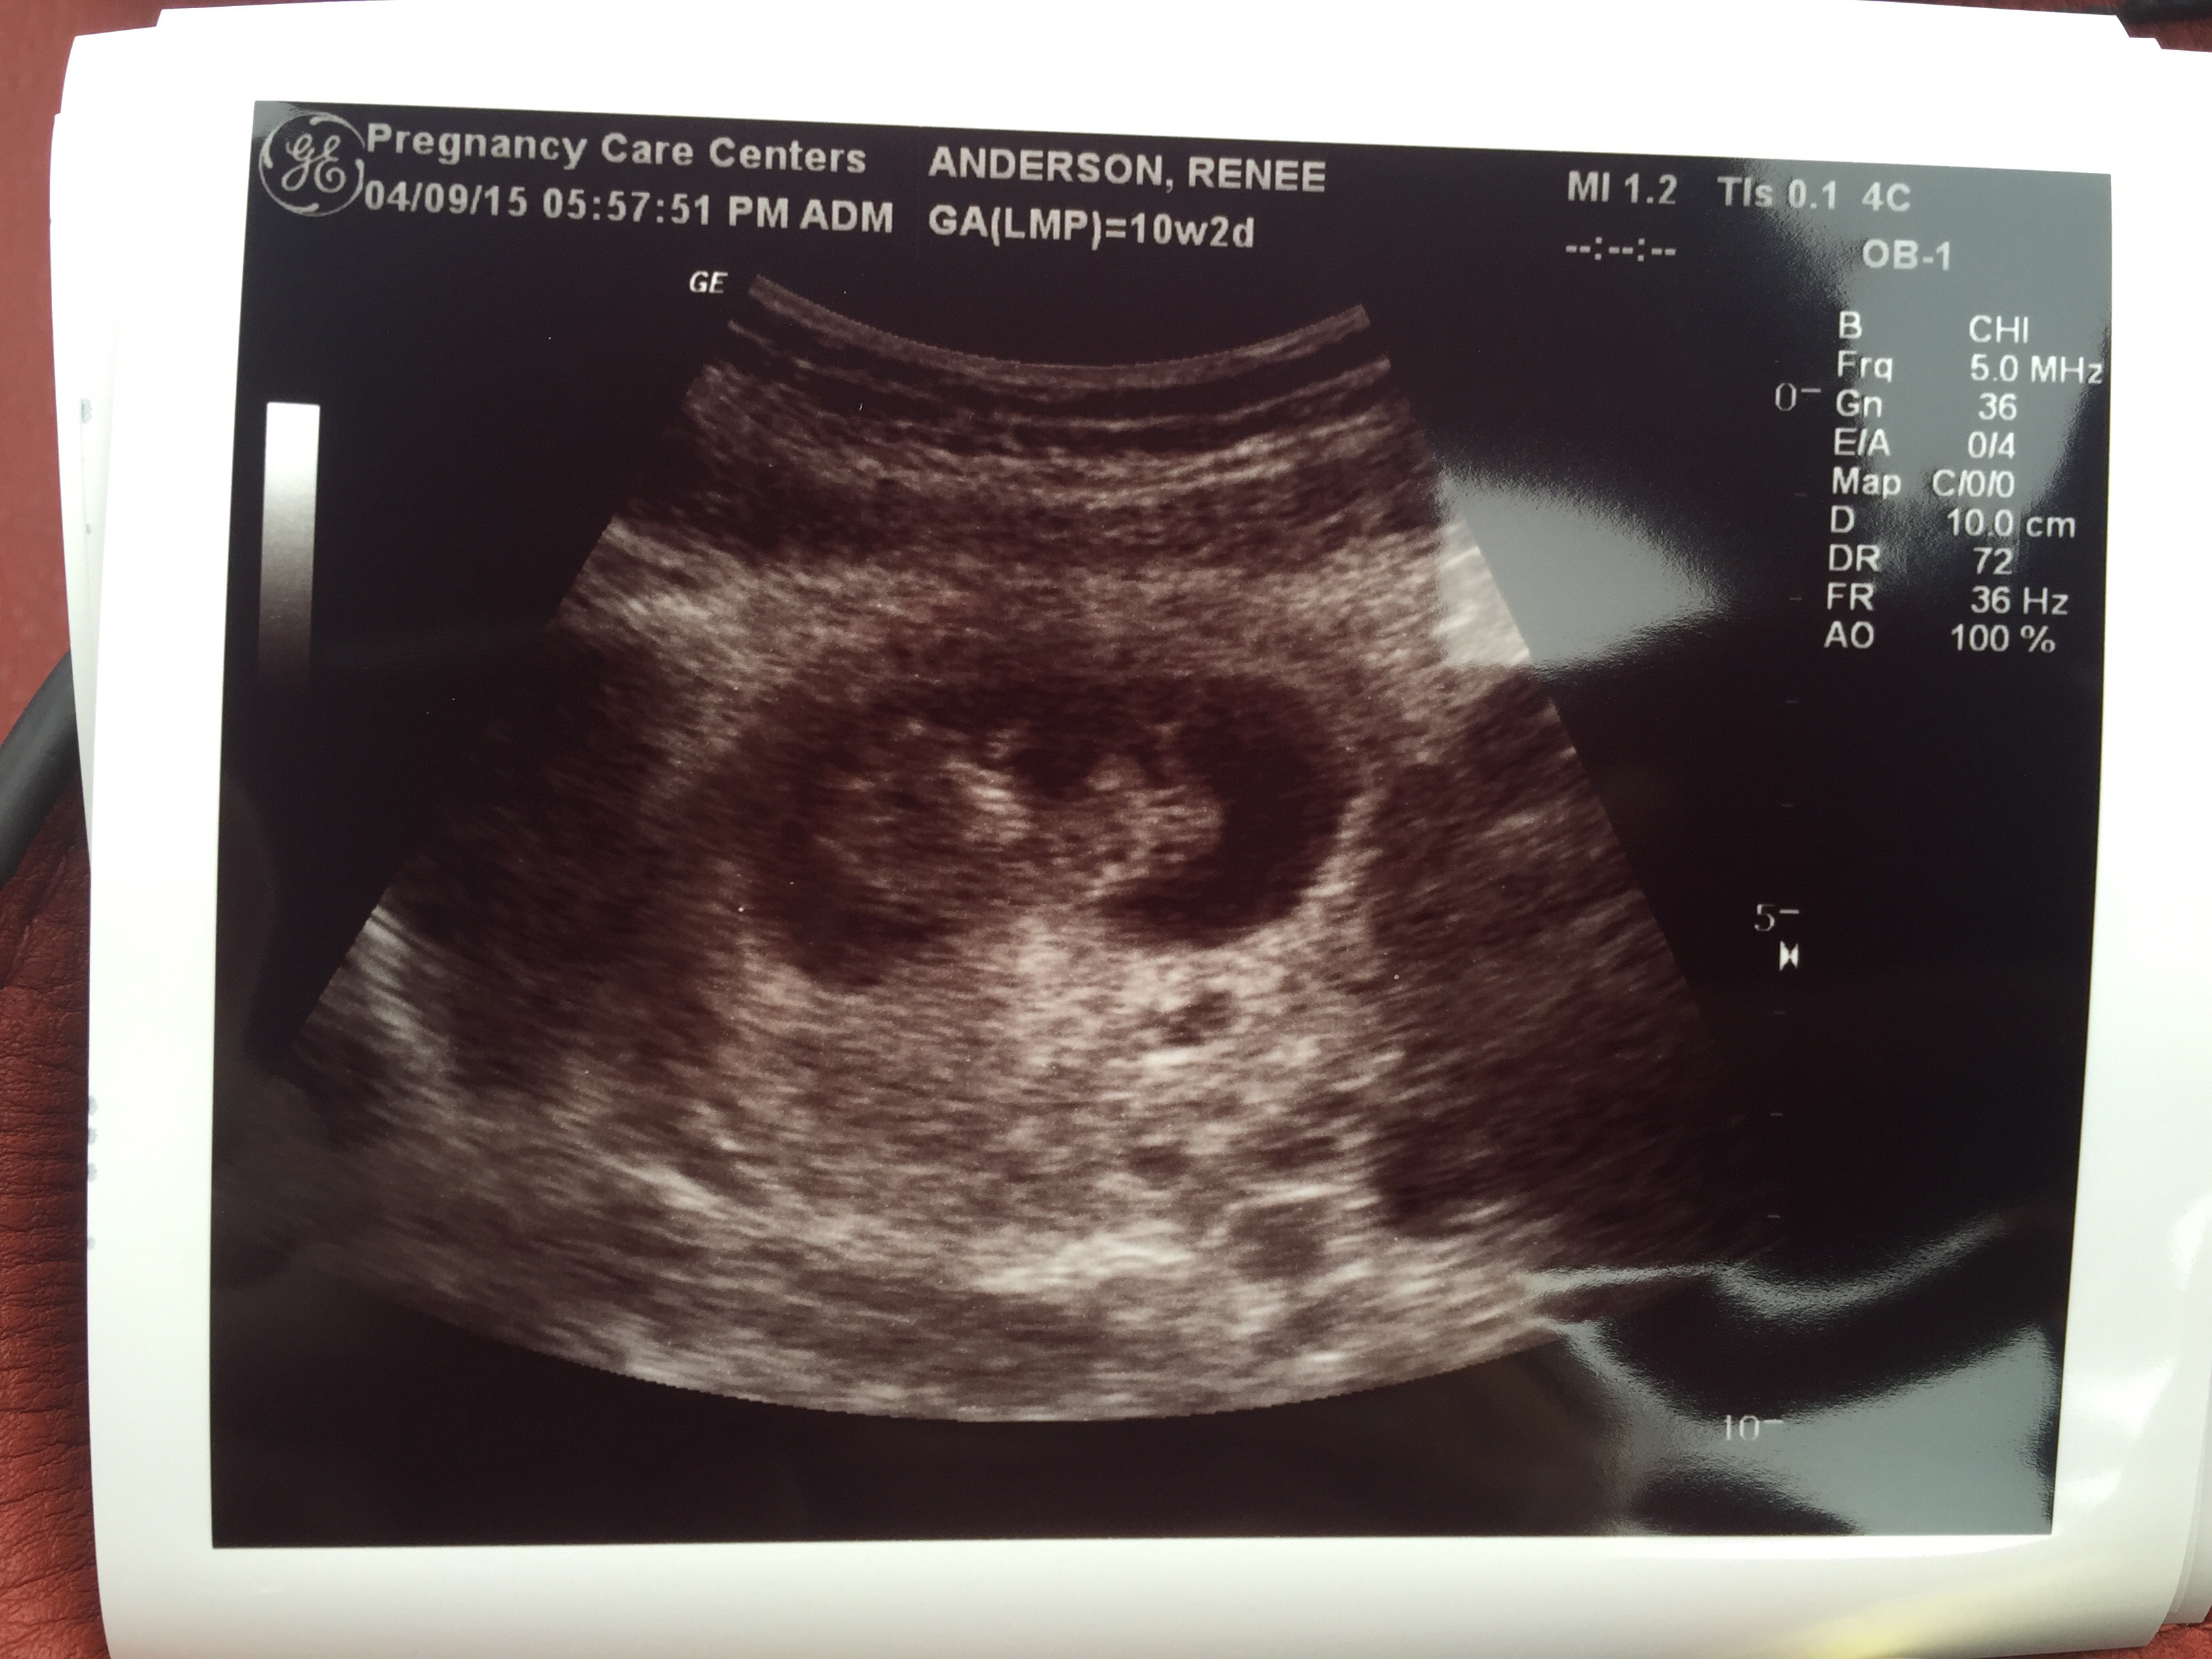

First in ER @ 8 weeks when I had spotting. HR 178. Best sight ever.

2nd @ 10 weeks. Measured 4 cm.

I get my NT screening on friday.